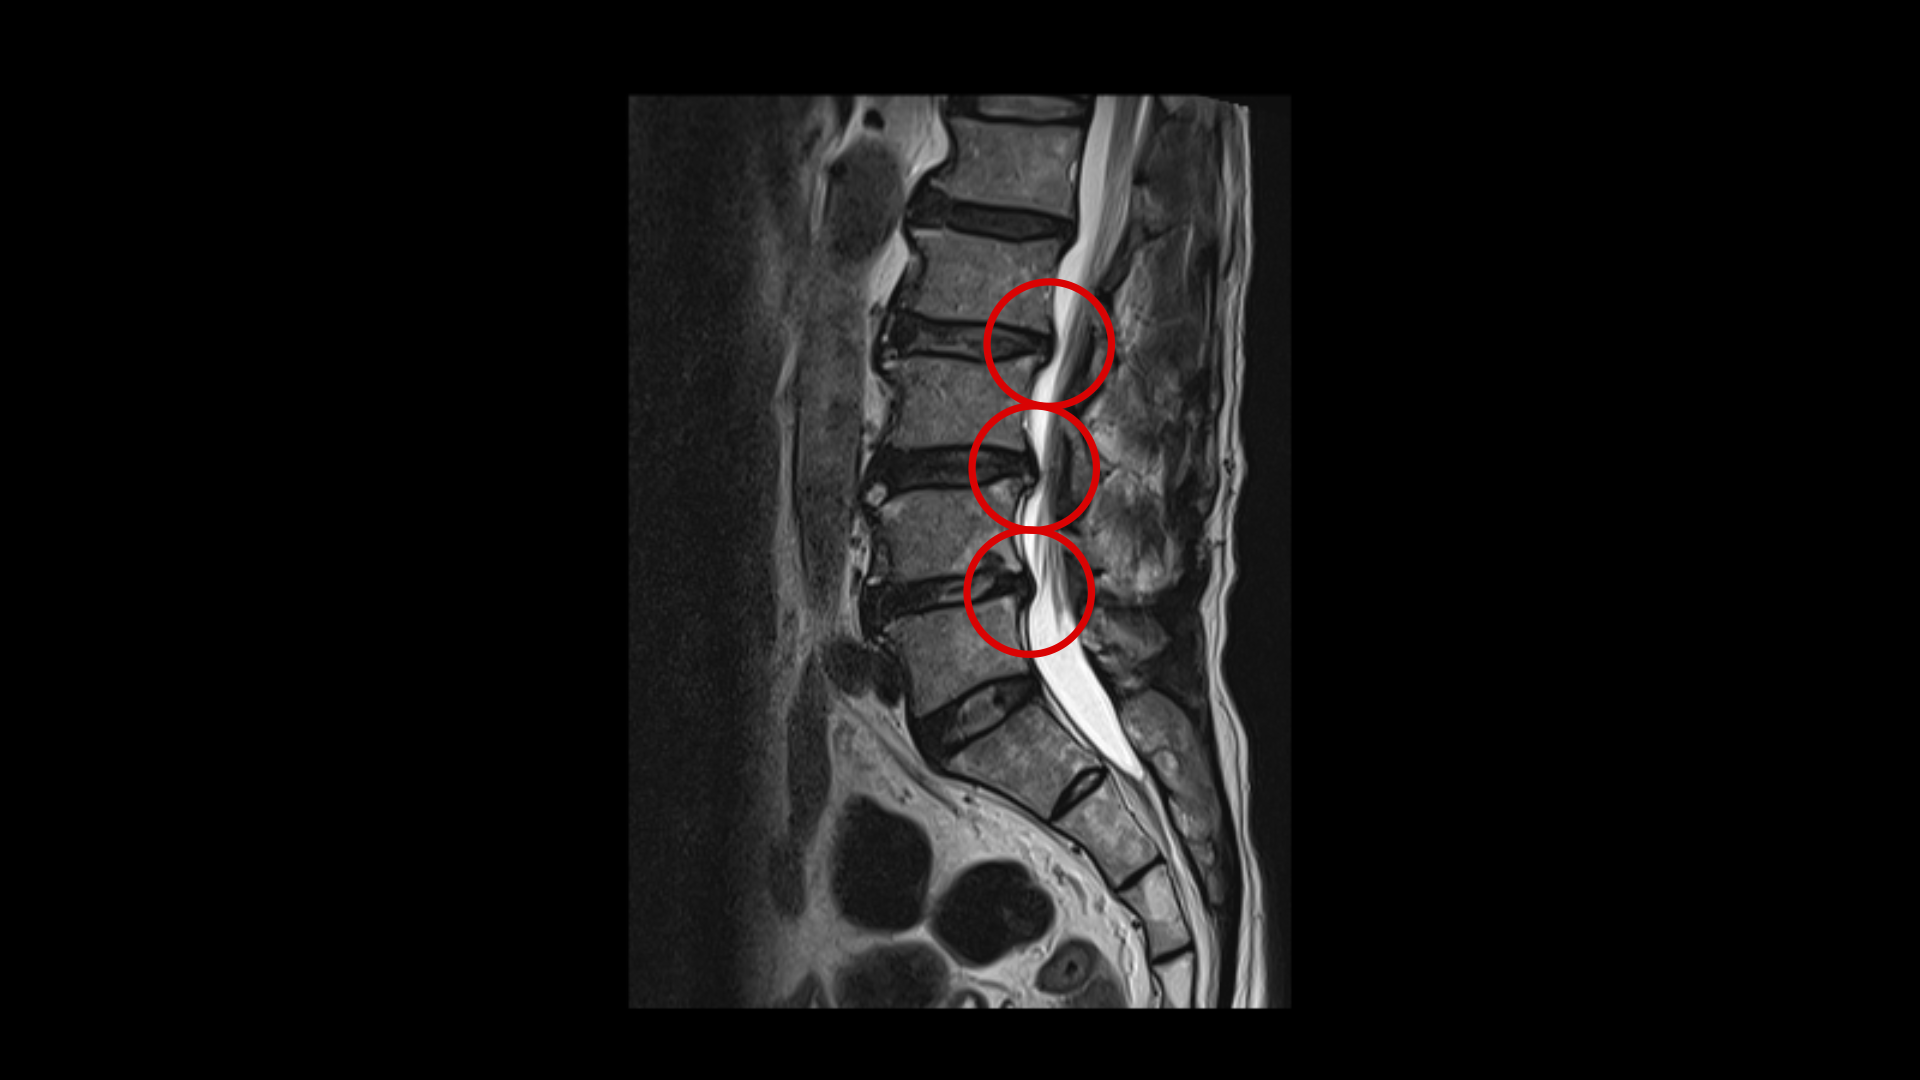

이 환자분은 두 달 전쯤 갑자기 허리가 아프면서 왼쪽 다리에 방사통이 생기면서 발목에 마비 증상이 발생했습니다. MRI를 보면 허리의 여러 마디에 퇴행성 디스크 및 디스크 탈출이 있고 특히 3번 4번과 4번 5번 마디에는 척추관협착증이 있습니다.

MRI를 다시 보면 4번 5번 마디에서 왼쪽으로 나가는 신경구멍이 밀려나온 디스크와 협착으로 인해 좁아져 있습니다. 다리마비와 방사통은 이것 때문에 발생한 증상으로 보입니다.